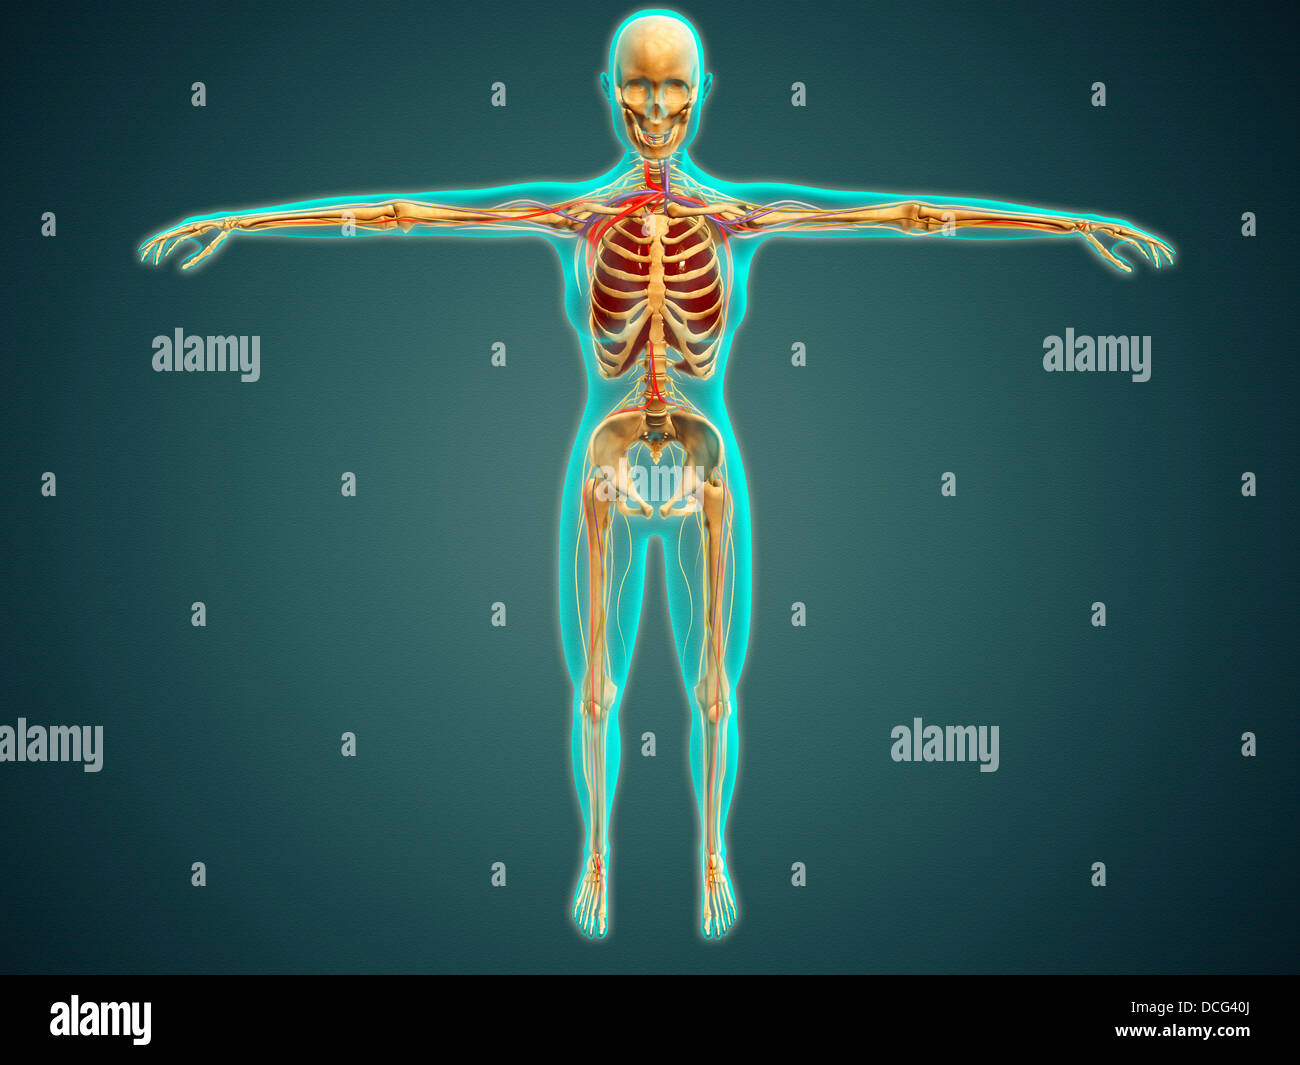

Medical illustration of human body showing skeletal system, arteries, veins, and nervous system. Stock Photohttps://www.alamy.com/image-license-details/?v=1https://www.alamy.com/stock-photo-medical-illustration-of-human-body-showing-skeletal-system-arteries-59361362.html

Medical illustration of human body showing skeletal system, arteries, veins, and nervous system. Stock Photohttps://www.alamy.com/image-license-details/?v=1https://www.alamy.com/stock-photo-medical-illustration-of-human-body-showing-skeletal-system-arteries-59361362.htmlRFDCG40J–Medical illustration of human body showing skeletal system, arteries, veins, and nervous system.